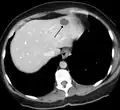

A liver hemangioma as seen on CT

Liver

Infantile hemangiomas in the liver are found in 16% of all liver hemangiomas. Its sizes are usually less than 1 to 2 cm in diameter. It may show a "flash-filling" phenomenon in which there is a fast enhancement of the contrast material in the lesion instead of slow, centripetal, nodular filling of the lesions in usual hemangiomas. On CT and MRI, it shows rapid filling during arterial phase, with contrast retention in venous and delayed phases.[40]